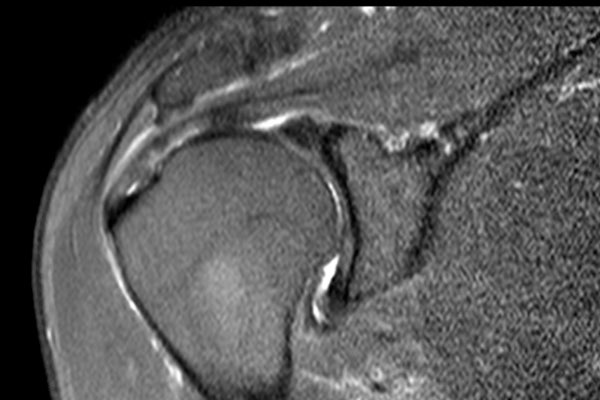

Nhấp vào hình ảnh để phóng to, sau đó cuộn qua các lát cắt.

Có hình ảnh rách toàn bộ chiều dày gân cơ trên gai kèm co rút và teo cơ.

Lưu ý các dải mỡ trong cơ tròn bé, cơ trên gai và cơ dưới gai.